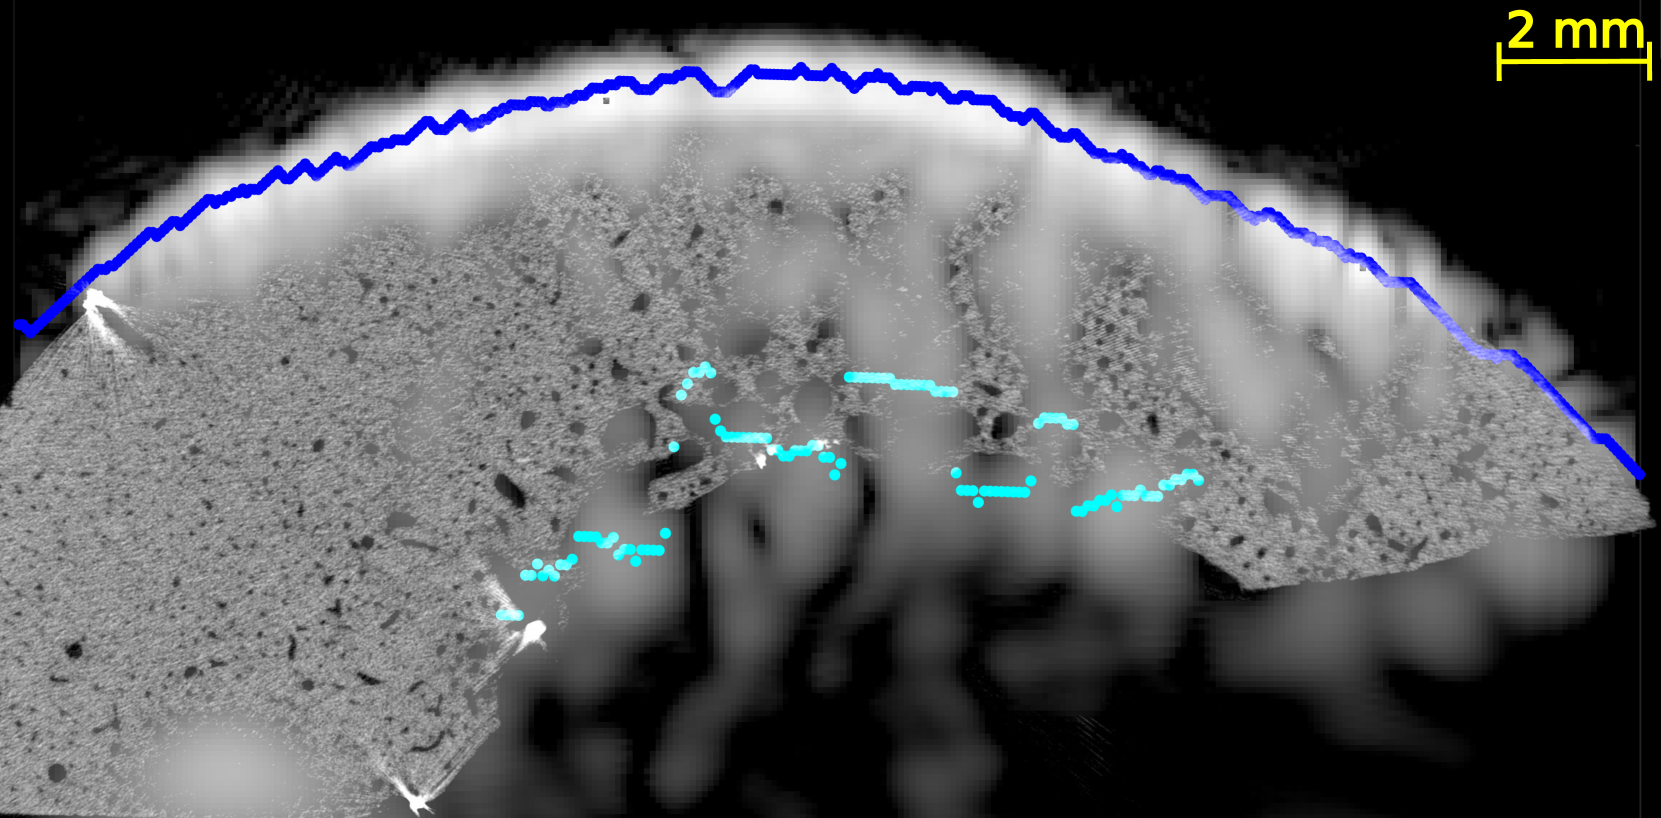

In all US images (Figure 4 and Figures S2-5 of supplementary materials), the periosteal surface appeared as a very bright line. The brightness of the endosteal surface was found to decrease with increasing porosity and with the presence of large pores. The endosteal surface was relatively bright in Samples 1 and 2 which had a small number of large pores and a small porosity; while the contrast of the endosteal surface was relatively weak in Samples 3 and 5 which had a higher porosity and some large pores near the endosteal surface (see the HR-µCT images (panels (a), (d), (g) and (j) of Figure 4). Segmentation with Dijkstra’s algorithm successfully delineated periosteal and endosteal surfaces for all measurement zones in all samples (see Figure 4). US images were aligned on HR-µCT images based on the periosteal surface segmentation. Periosteal surfaces from the US images accurately matched the periosteal surfaces segmented from the HR-µCT images: for all VOIs and all measurement repetitions, the root mean square error (RMSE) between the two segmentations was smaller than 0.3 mm, which value corresponds to half a US wavelength in water at 2.5 MHz (i.e., approximately the resolution limit).

We observed a good match between the segmented endosteal surface in the US image and the boundary of the cortex as seen in the HR-µCT image. The segmented endosteal surface closely followed the shape of the bone in the samples 1 and 2 which were the less porous and less heterogeneous. It is noteworthy that, despite the large thickness and complex geometry of sample 2, the endosteal surface was very bright in the US image. In the more porous and heterogeneous samples 3 and 5, the segmented endosteal surface followed the gross shape of the bone but was inside the cortex as seen in the HR-µCT image, above some large pores found close to the endosteal cortex boundary.

We evaluated the quality of US anatomical reconstructions and wave speed measurements across sixteen VOIs from bones of four individuals. Indeed, the bone of a fifth individual (sample 4) was too porous and heterogeneous to be effectively imaged through US. Our results indicate that the cortex boundaries and cortical thickness can be accurately determined for homogeneous and moderately porous VOIs, even for a thick cortex, as observed in samples 1 and 2 (mean thickness 2.9 and 5.9 mm and porosity between 5.0 and 12.3%, respectively). In these cases, the overlaying of US and HR-CT images showed that the segmentation of the surfaces in US images with the Dijkstra’s method closely aligns with the actual boundary, achieving thickness measurements with mean relative errors of 9 % and 4 %, respectively. In regions with higher porosity and larger pore diameters (samples 3 and 5 with porosity between 10.9 and 16.6% and Lg.Po.Dm between 224 and 307 m, respectively), the brightness of the endosteal surface is significantly reduced (from 7 dB to -5 dB). Nevertheless, Dijkstra’s algorithm was able to delineate endosteal boundaries that generally lied within the cortex, above the region with very large pores nearest to the endosteal surface. Consequently, in these cases, US-based cortical thickness measurements underestimated the reference (mean relative errors of 32 % and 47 %). However, for these highly remodeled bones with large resorption cavities leading to a trabecularization of the endosteal region, the delineation of the endosteal boundary as the end of the cortex and the beginning of the medullary canal is ambiguous, making it challenging to obtain a meaningful estimate of cortical thickness in the HR-CT images [5]. Another limiting factor in comparing cortical thicknesses determined from HR-CT and from US images lies in the slight differences in the regions of interest used for each VOI. The region of interest used for HR-CT images (Figure 2) were slightly larger than that used for US images. In the latter, as shown in Figure 4, the surfaces could only be reconstructed for a limited portion of the cortex due to the finite US probe aperture.

It is noteworthy that the inner cortex surface reconstructed with US was consistently within the bone, indicating that it effectively detects the most compact region corresponding to the tissue above the large pores in the endosteal region.

In highly porous samples exhibiting large pores, the reconstructed endosteal surface may show a reduced brightness and a lack of continuity. Indeed, previous simulations demonstrated that increased pore size has a strong detrimental effect on endosteal interface brightness [29], primarily due to the enhanced scattering by large pores. This ex vivo study corroborates these simulations results by providing an experimental proof that pore size is a major factor influencing intracortical US image quality.